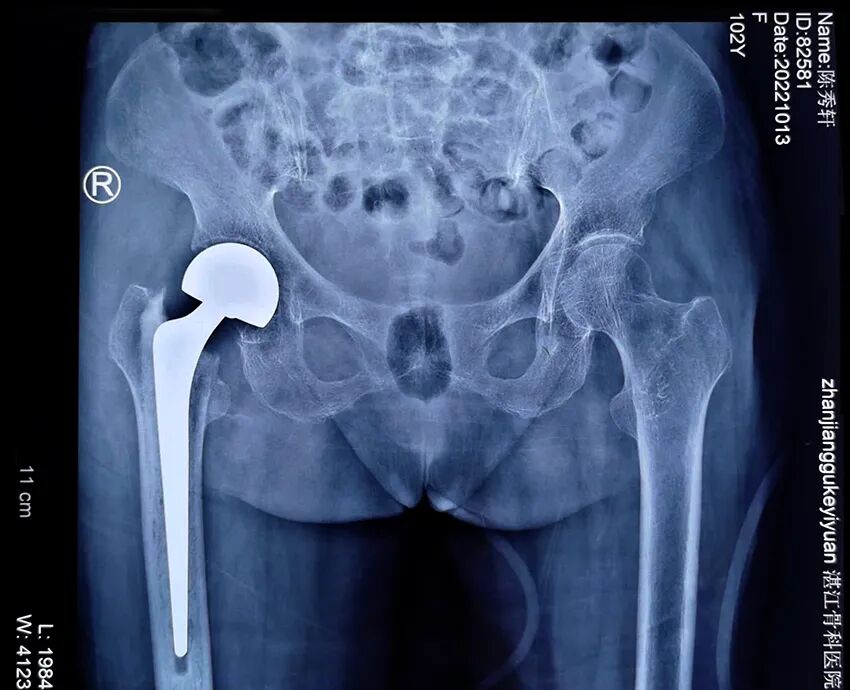

患者陈某,女性,身份证年龄102岁,实际年龄103岁,家住廉江横山镇某村。

入院:2022年10月8日;出院:2022年10月19日。

患者在家中不慎摔倒致右股骨颈骨折,不能站立及行走。家属送去多家医院都因年龄大,并发症多,拒绝接收,后通过朋友了解到到湛江骨科医院技术力量强、设备精良,多项骨科技术在粤西地区处于领先地位,特别是在老年髋部骨折手术治疗方面有丰富的经验,后慕名送到湛江骨科医院。

术前图像

术后图像